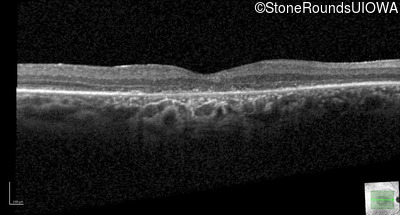

Optical Coherence Tomography - Left - 20/20 sc

Exemplar / OCT Stack